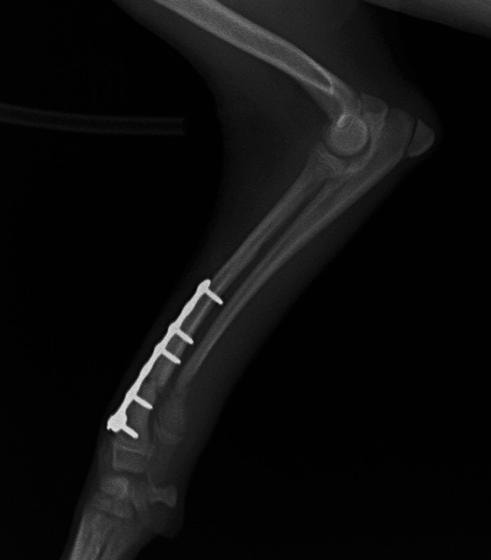

トイプードル 右遠位橈尺骨短斜骨折のALPSによる内固定

Locking Compression Plate

LCPは、スクリュー(ネジ)とプレート(金属の板)をロックする特殊な構造により骨折部位を固定する新しい世代のプレートシステムです。ひとつのホールでロッキングスクリューとスタンダードスクリューの使用を選択できるユニークな構造をしているため、骨折断端間の圧迫を目的とした従来型プレート固定法に加え、高い角度安定性を有するロッキングスクリューを用いた固定法の選択が可能です。従来のプレートシステムでは困難だった部分の骨折や癒合不全の症例に高い治療効果をもたらします。